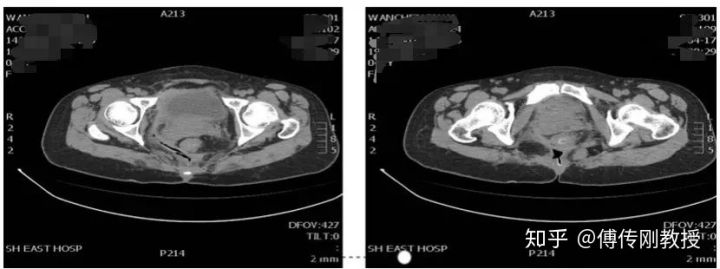

腹部CT

好景不长,我出现肛周疼痛,医生给我查体显示骶尾部可见巨大瘢痕,可及一外口,探查长约15cm左右,无渗血,直肠指诊齿状线上5cm触及粪块,指套无染血。医生诊断为:盆腔畸胎瘤(经骶切除术后),乙状结肠造口术后,盆腔巨大囊肿。